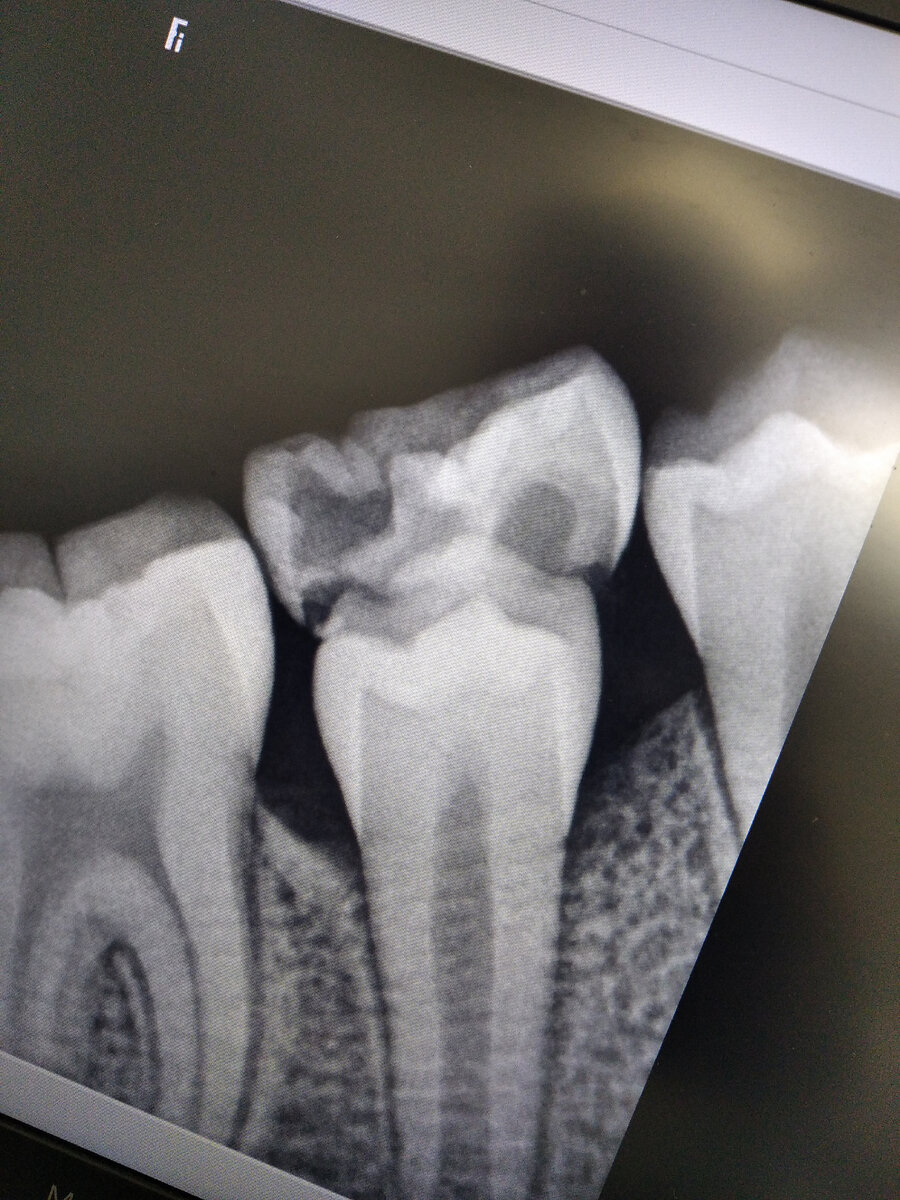

Бывает ещё так, что вроде зуб по возрасту должен выпасть, но он не выпадает, при этом шатается, чаще всего, этот зуб может быть зажат двумя соседними зубами или же корни зуба не рассосались до конца, например как на фото. 👇

На фото зуб у которого рассосался только один корень.

Например постоянный 4 зуб ( премоляр) растёт немного в наклоне, в сторону 3 зуба ( клыка), соответственно получается так что у молочного 4 зуба из 2 корней рассасывается только один.